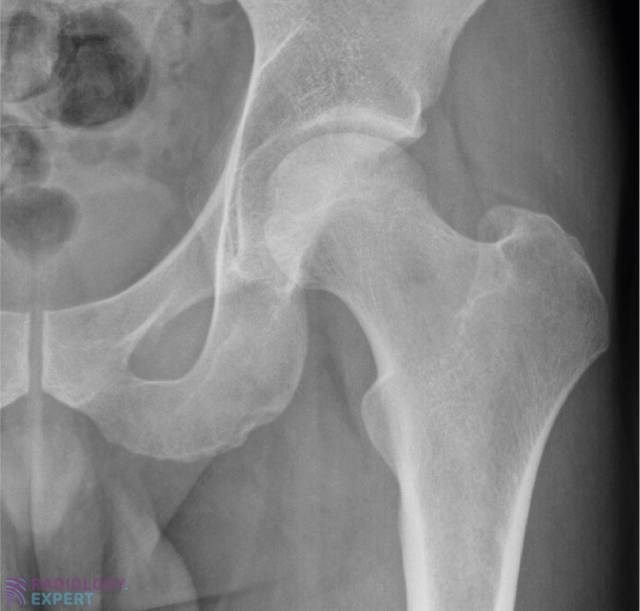

Normal anatomy AP image of the hip Normal anatomy AP image of the hip

Click image to see overlay